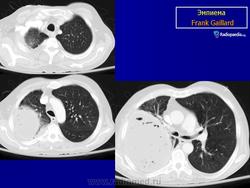

Эмпиема плевры.

Гнойным плевритом или эмпиемой плевры называют скопление гнойного выпота в плевральной полости.

Рентгенодиагностика

В большинстве случаев при развитии гнойного плеврита выпот вначале скапливается в наддиафрагмальном пространстве, в его наиболее низко расположенных отделах - синусах. В связи с этим первыми рентгенологическими признаками наличия жидкости в плевральной полости служат сглаженность реберно-диафрагмального синуса на рентгенограммах в прямой и, особенно, в боковой проекциях и кажущееся высокое положение купола диафрагмы. Массивная воспалительная инфильтрация нижней доли легкого может затруднить выявление этих симптомов. В этом случае рекомендуют сделать рентгенограмму в положении пациента лежа на больном боку. При этом жидкость распределяется вдоль грудной стенки и становится хорошо видимой. Это позволяет не только подтвердить наличие выпота в полости плевры, но и приблизительно определить его объем. При толщине полосы жидкости более 10 мм количество последней составляет более 200 мл и при плевральной пункции ее можно аспирировать шприцом. Однако этот прием срабатывает только при свободной от сращений плевральной полости, равно как и появление косой верхней границы затемнения, известной как линия Эллиса-Дамуазо, возникающей при увеличении объема выпота. Дальнейшее накопление экссудата приводит к нарастающему затемнению и смещению средостения в противоположную сторону. Последний признак, однако, отмечается лишь в тех случаях, когда легкое в связи с воспалительной инфильтрацией теряет свою эластичность и не спадается под давлением окружающей его жидкости, либо при очень большом объеме выпота.

По распространенности и локализации выделяют тотальные эмпиемы, захватывающие всю плевральную полость от купола до диафрагмы, распространенные, при которых эмпиема ограничивается двумя или тремя анатомическими стенками плевральной полости (например, реберной и диафрагмальной, или медиастинальной, диафрагмальной и реберной) и ограниченные, в образовании которых принимает участие одна плевральная стенка. По локализации такие эмпиемы бывают пристеночными, апикальными и базальными.

Эмпиема.